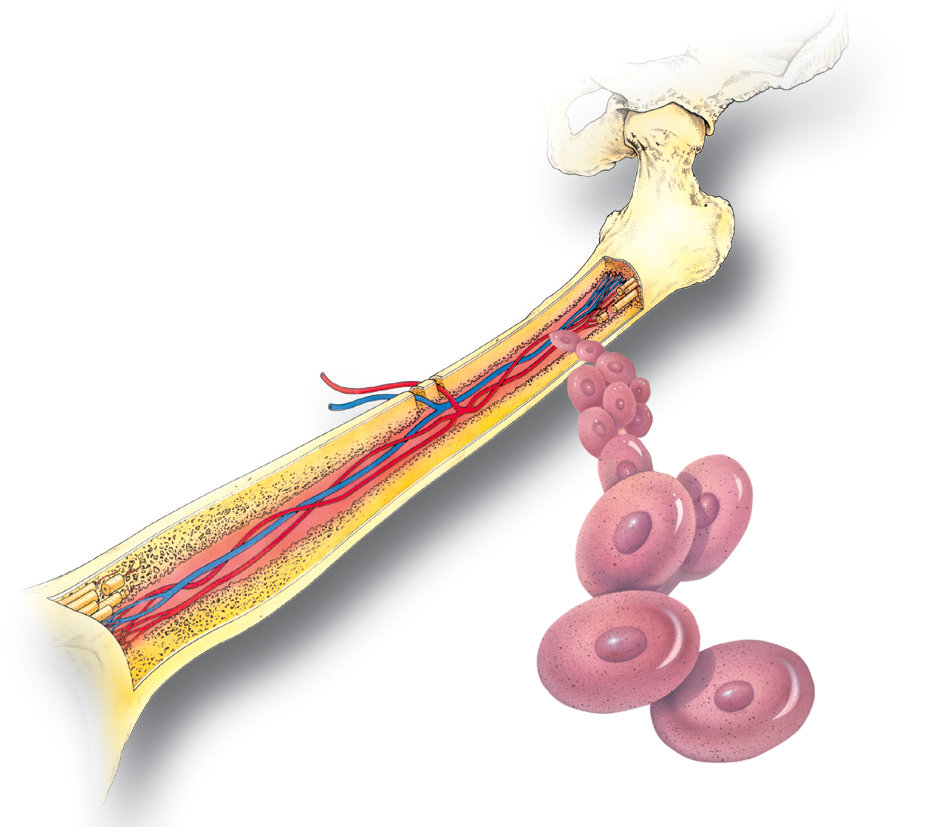

Изучение костного мозга: анатомия и функции